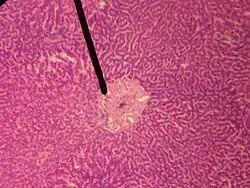

![]() human central vein | |

The central veins of liver (or central venules)[1] are veins found at the center of hepatic lobules (one vein at each lobule center).

They receive the blood mixed in the liver sinusoids and return it to circulation via the hepatic veins.[2]